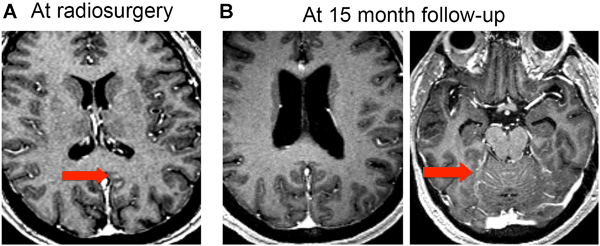

19+ Small Cell Lung Cancer Brain Metastases Srs PNG. Approximately 10% to 18% of patients present with brain metastases (bm) at the time of initial diagnosis, and an additional 40% to. It tends to disseminate early in the course of its natural history and to grow quickly.

Brain metastases are a common complication in a wide range of cancers, but they are particularly common among patients with lung cancer. Small cell lung cancer (sclc) comprises about 20% of lung cancers diagnosed in the united states. This growth can spread beyond the lung by the process of metastasis into nearby tissue or other parts of the body.